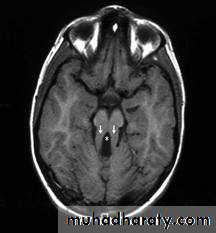

MRIDelineate structural malformations

Neuronal migration defectsAbnormal signals in the basal ganglia (mitochondrial abnormalities) or brain stem defects (Joubert syndrome)

Deep white matter changes can be seen in Lowe syndrome, a peroxisomal defect

Abnormalities in the corpus callosum may occur in Smith- Lemli-Opitz syndrome

Heterotopias may be seen in congenital muscular dystrophy.

Magnetic resonance spectroscopy

Magnetic resonance spectroscopy also can be revealing for metabolic disease.Radiologic evaluation